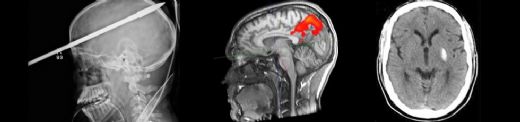

Düşme Sonucu Beyin Kanaması Belirtileri ve TedavisiDüşme, pek çok insanın hayatında karşılaşabileceği yaygın bir durumdur. Ancak bazı düşme vakaları, ciddi sonuçlara yol açabilir. Bu makalede, düşme sonrası ortaya çıkabilecek beyin kanaması belirtileri ve tedavi yöntemleri ele alınacaktır. Düşme Sonrası Beyin Kanaması Nedir? Beyin kanaması, beynin içindeki veya çevresindeki kan damarlarının yırtılması sonucu meydana gelir. Düşme gibi travmatik olaylar, bu tür kanamalara yol açabilir. Beyin kanaması, intracerebral (beyin içinde), subaraknoid (beyin zarları arasında) veya epidural (beyin zarlarının dışındaki kanama) olarak sınıflandırılabilir. Bu tür kanamalar, beyin dokusuna zarar verebilir ve ciddi sağlık sorunlarına yol açabilir. Beyin Kanaması Belirtileri Düşme sonrası beyin kanaması belirtileri oldukça çeşitli olabilir. Bu belirtiler, kanamanın yerini ve büyüklüğünü etkileyen faktörlere bağlı olarak değişiklik gösterebilir. Aşağıda, düşme sonrası beyin kanaması olasılığını işaret edebilecek bazı yaygın belirtiler sıralanmaktadır: